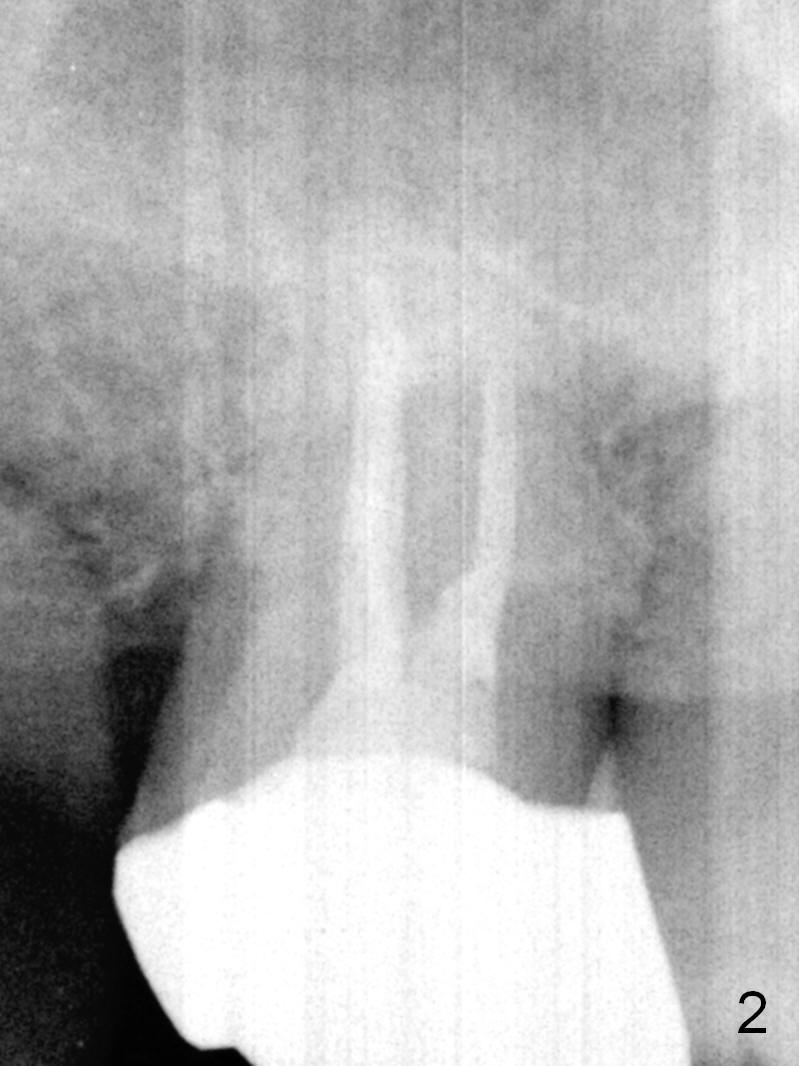

A 52-year-old man has had mild cold sensitivity for the last 3 years since RCT was done at the tooth #2 (3 canals, MB2 not found, Fig.1 (preop), 2 (taken today, pain more severe)). After discussion of treatment options (including RCT retreat), the patient chooses extraction and implant. The planned implant is 6.5x9 mm (Fig.3). As expected, the 3 roots are fused (Fig.4). The socket is single and triangular (Fig.6 green outline (black one: gingival margin)). What is not really expected is the presence of the possible MB2 canal (Fig.5 *). The mesiodistal width of the buccal roots and palatal one are 6.5 and 4.5 mm, respectively. The diameter of the planned immediate implant is estimated to be 5 mm. The socket depth is 11 and 13 mm to the crest and the gingiva, respectively. After use of Magic Expanders (ME) from 3.0-4.3 mm for sinus lift, a 5x11 mm dummy implant is placed. The implant (Fig.7 red circle) has 3 pointed contact so it is stable, but it is placed apically (Fig.8). After removal of the dummy implant, allograft is placed (.5-1.5 mm) before insertion of a 5.5x11 mm implant with satisfactory stability (Fig.9). Postop, the patient reports light bloody nasal discharge with bone graft. Ideally with the narrow mesiodistal socket, it is unnecessary to penetrate the sinus floor with ME. A 5x9 mm dummy implant should have been placed with well-controlled implant placement depth. It is followed by inserting an implant .5 mm larger for the maxilla. IBS implants are easy to achieve primary stability. Insertion torque of 20 Ncm is sufficient to load abutment (5x4(4) mm) and immediate nonfunctional provisional.